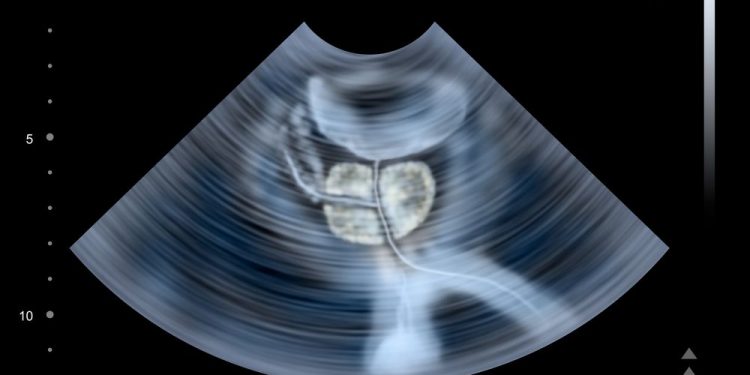

In a nerve-sparing procedure, your surgeon will use a robot-guided instrument with a camera and loop of wire that is passed into your urethra. The camera lets your surgeon see the area and the loop of wire, which can be used to cut away any part of the prostate that is causing symptoms or blocking the urethra. Your doctor will probably also take out some lymph nodes that are nearby the prostate, which can help to check for cancer cells and to decide if you need any other treatment.

Your doctor might advise a radical prostatectomy, which is an operation to remove the entire prostate. If you have a small tumour, your surgeon might be able to do this through keyhole surgery. They will insert a tube into the urethra and, with the help of a camera, guide a loop of wire or a hollow metal rod down to your prostate. They will then use the device to remove your prostate, leaving a scar on your tummy.